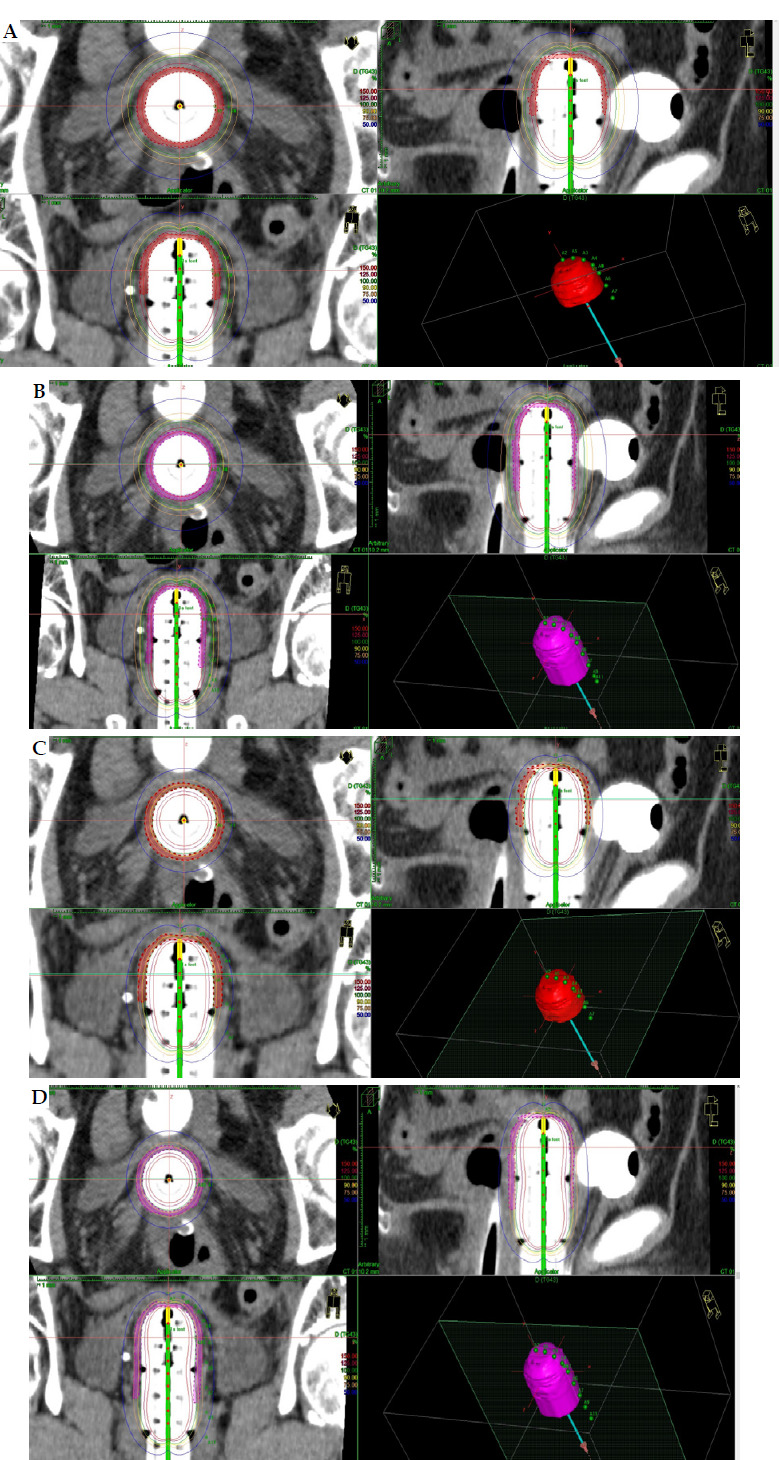

Material and methods: Three different computed tomography (CT) studies for vaginal cylinders of 3.5 cm, 3 cm, and 2.5 cm were performed. Clinical target volume (CTV) was delineated for 3 cm and 4 cm of vaginal length. Twelve schedules were analyzed obtaining overall vaginal surface dose (Gy) (EQD2 α/β = 10 and α/β = 3), overall D90 CTV (α/β = 10) (Gy), and overall D2cc (α/β = 3) for organs at risk (OARs), such as vagina, rectum, sigmoid, rectum, and bladder. Prescription at 5 mm from the applicator surface and at the surface were analyzed for each case.

Results: The overall vaginal surface dose and dose to CTV varied widely among the different schedules, and CTV delineation was necessary in case of surface prescription. The applicator diameter of 3.5 cm showed the best dosimetry results for vaginal surface dose. The overall D2cc OARs' doses changed in the different CT studies.

Abstract Image